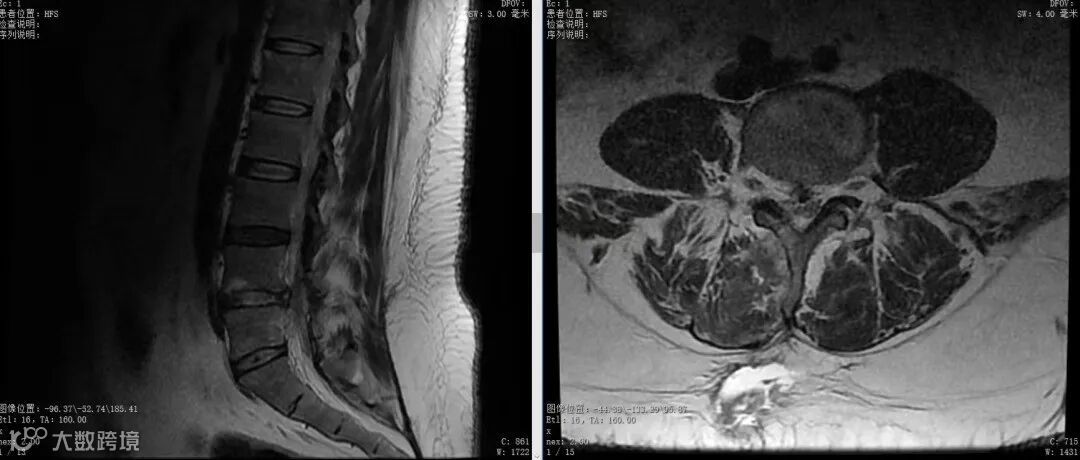

刘先生术前磁共振

骨科主任路江鸿带领团队迅速行动起来,对刘先生进行了详尽的查体,发现患者已出现了足背感觉及背伸肌力下降的神经损害症状,结合磁共振见腰4/5椎间盘巨大突出压迫腰5神经根,症状体征及影像学均高度统一。已无保守治疗可能,结合患者体重特殊(300多斤)的个体情况,决定行UBE内镜手术(单侧双通道脊柱内镜技术)。